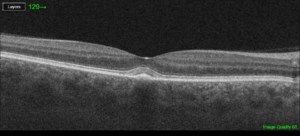

Jeg ser ind imellem patienter i min klinik med Adult Vitelliform Macular Dystrofi. De vedlagte billeder er dels foto af øjets centrale nethinde, hvor forandringen ikke er synlig og et OCT-billede fra samme øje, hvor forandingen ses som den lyse hævelse midt i billedet.